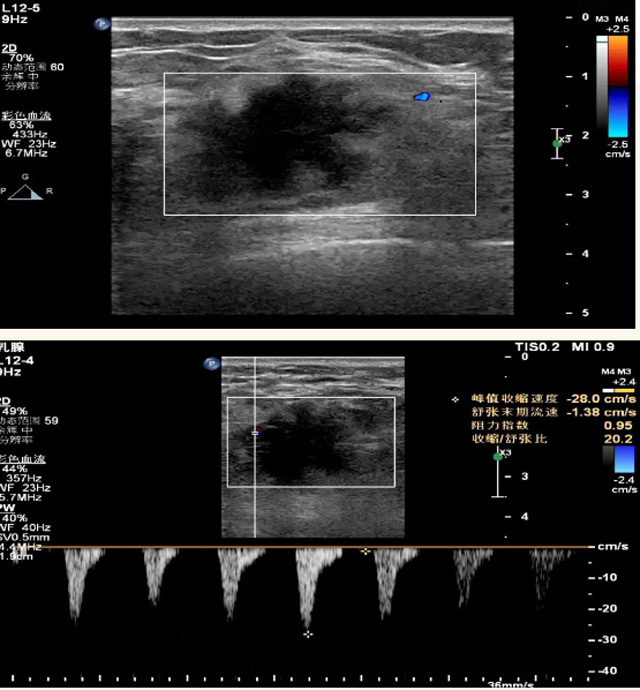

乳腺B超檢查無輻射,對囊性病變敏感,可以實時觀察病灶。超聲引導(dǎo)活檢跟手術(shù)前的定位。就是它對于微小的鈣化查出率比鉬靶稍微差點。磁共振MRI檢查也是是沒有輻射的,對備孕跟已經(jīng)懷孕的人士比較友好。不用擔心這個輻射影響胎兒問題。對乳腺病灶敏感性較高,致密乳腺病灶、乳腺癌的復(fù)發(fā),準確鑒別囊性及實性病變。可以幫助臨床醫(yī)生判斷惡性、良性病變。但是MRI磁共振對微小鈣化不明顯,微鈣化還是鉬靶靠譜點。檢查時間比較長,有偽影的影響。費用相對B超,鉬靶高很多。

乳腺B超